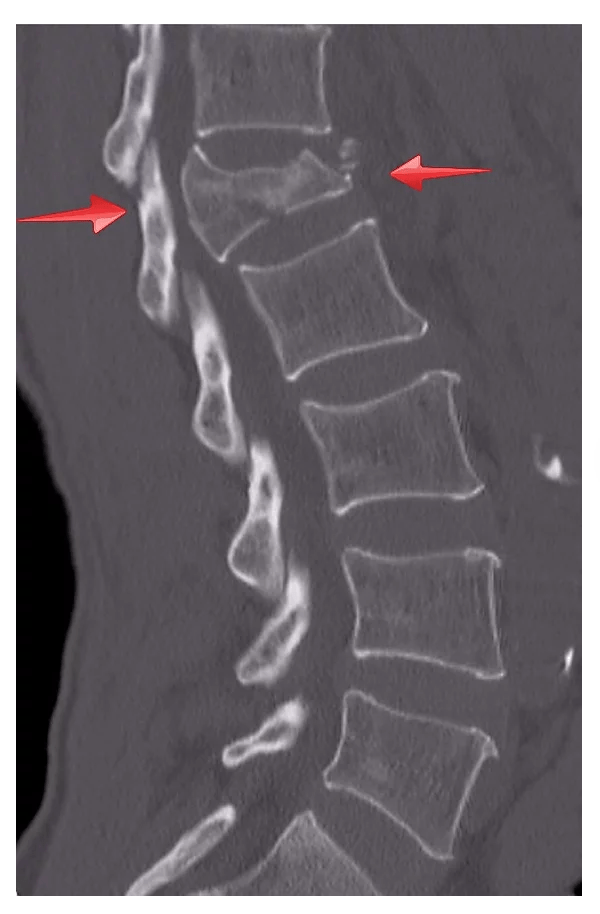

Kırıklar: Bir kemiğin üzerine dayanabileceğinden fazla yük binerse o kemik kırılır. En sık görülen tipi kırık omurun ön kısmının çöktüğü “çökme kırıkları”dır. Eğer omurga üzerine binen yük daha da şiddetli ise o zaman omurun orta ve arka kısmı da kırılabilir ve kırık parçaları omurilik kanalına doğru yer değiştirip omuriliği zedeleyebilir. Bu tip kırıklara da “patlama kırığı” denir. Patlama kırıklarında omurilik yaralanması ve felç sık görülmekle birlikte her patlama kırığı felce ya da omurilik yaralanmasına neden olmaz. Kırıklar genellikle tek bir omurda olmakla beraber %20-30 oranında ardışık veya ardışık olmayan birden fazla omuru da içerebilir.

Bilgisayarlı tomografi: Kırıkları röntgenden daha iyi gösterir. Bazı hastanelerde rutin uygulanmaktadır. Diğerlerinde ise röntgende görülen kırıkların şiddetini ve tipini değerlendirmek için istenebilir.